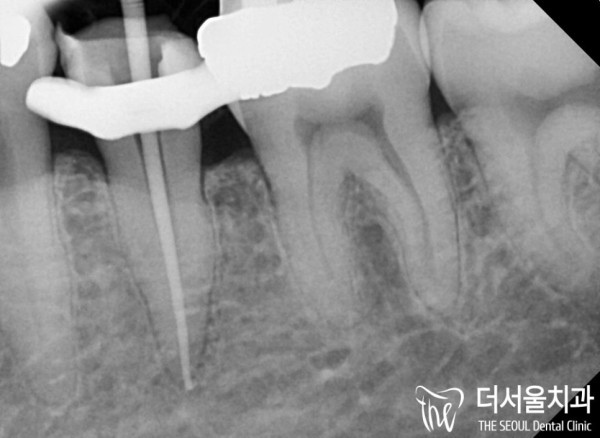

아말감 보철 밑으로 2차 충치가 생긴 모습이 확인됩니다.

치료 받은 곳에 다시 충치가 생기는것을 2차 충치라고 합니다.

이미 법랑질과 상아질을 뚫고 치수까지 감염이 일어난 상태로

통증이 많이 느껴지는 상태였습니다.

Secondary cavities are confirmed under the amalgam prosthesis.

The recurrence of cavities in the treated area is called secondary cavities.

It's already been infected through enamel and dentine to the pulp

I felt a lot of pain.

af9c1dfa2282fe1e804a6ffdbd4daa8e_1704422737_5135.jpg

이런경우 보통 임플란트까지 해야 할수도 있지만

이 환자분은 아주 정도가 심각하지는 않았기 때문에

자연치아를 살릴 수 있는 상태였습니다.

즉, 신경치료를 통해 자연치아를 살리기로 하였습니다.

감염이 생긴곳을 깨끗하게 청소하고

충전재료를 뿌리 끝까지 꼼꼼하게 채워넣었습니다.

이 과정에서 치수 속이 오염되거나 꼼꼼히 들어가지 않는다면

또다른 문제가 생길 수 있어 아주 신중하고 꼼꼼히 치료를 해야 합니다.